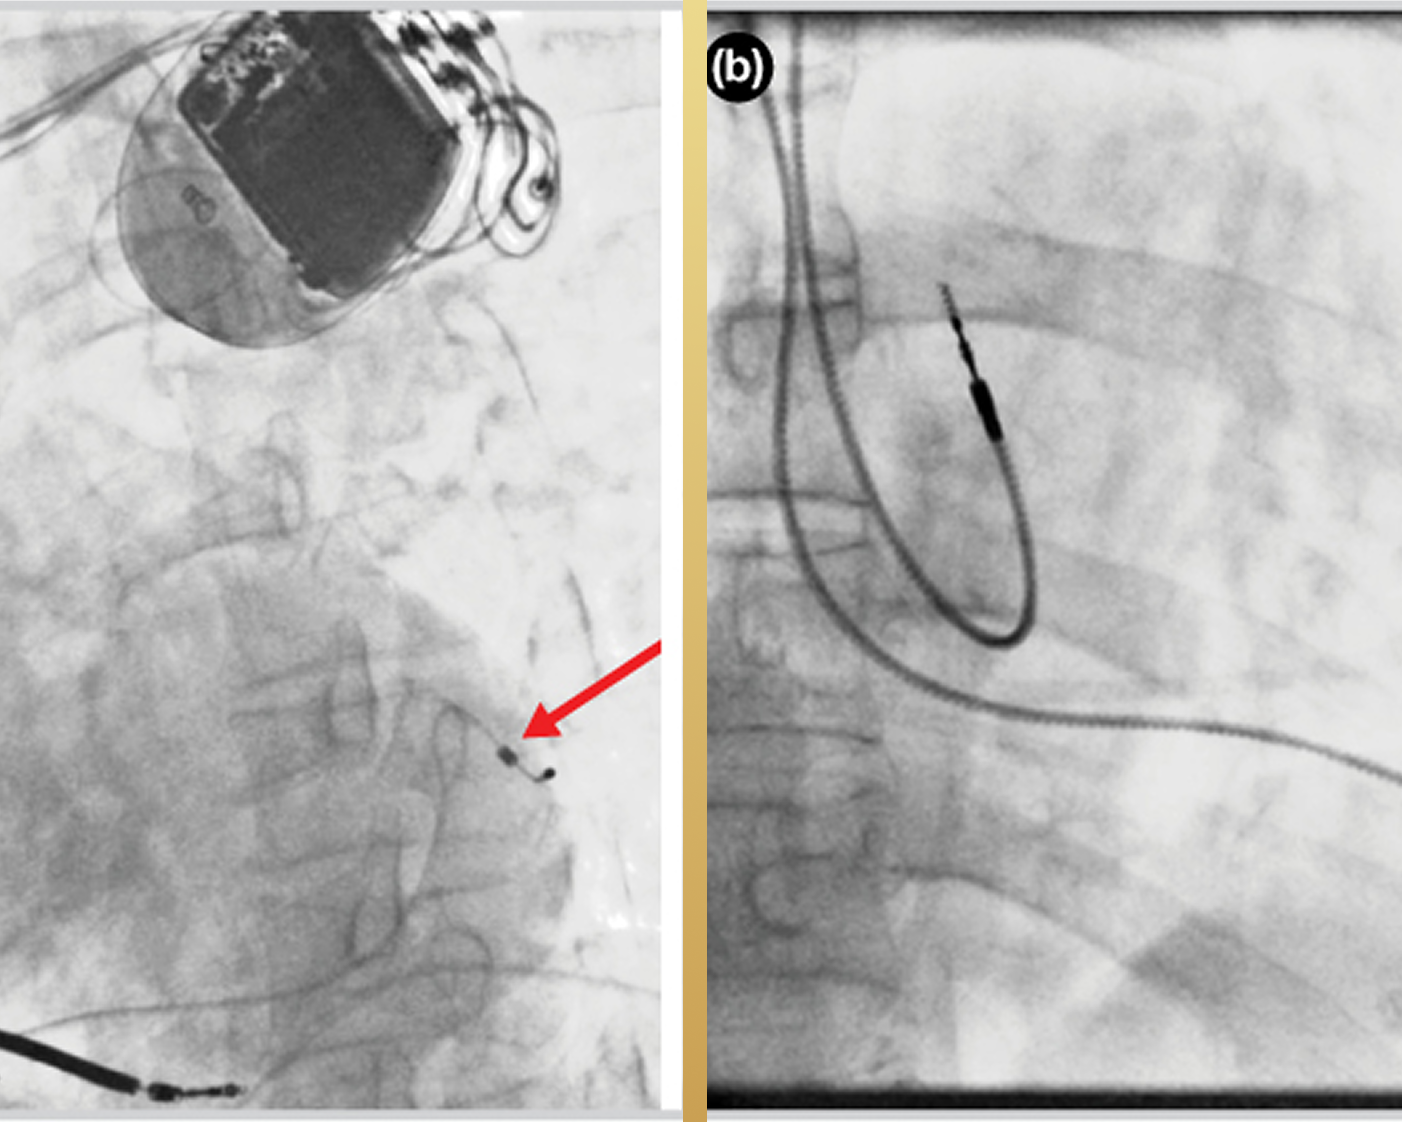

Advanced pacemaker procedures with precise placement and monitoring to improve heart rhythm and recovery.

Advanced CRT implantation to improve heart coordination with precision and monitoring for better outcomes.